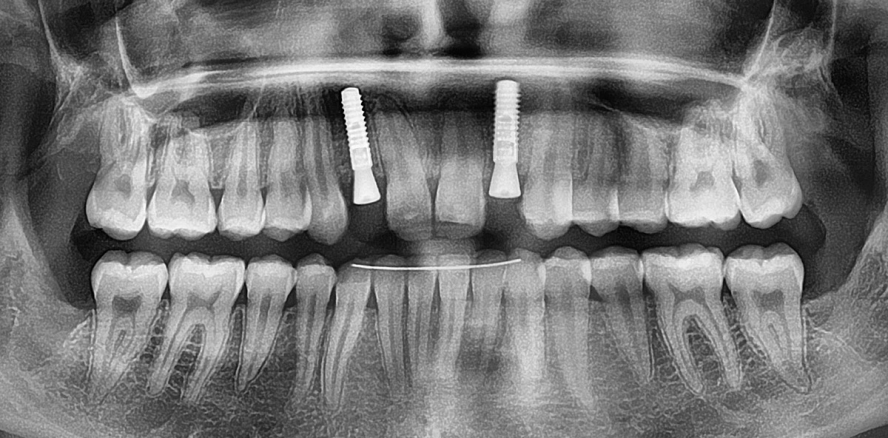

Eine 18-jährige Patientin kam mit dem Wunsch, aufgrund von Nichtanlagen bestehende Lücken Regio 12 und 22 durch implantatgetragenen Zahnersatz schließen zu lassen (Abb. 1 und 2). Hierbei stand neben der funktionellen Rehabilitation der Wunsch nach einer ästhetisch ansprechenden Lösung im Vordergrund.

Die klinische Untersuchung zeigte einen durch die kieferorthopädische Behandlung gut ausgeformten Zahnbogen, der genügend Platz für die Kronen Regio 12 und 22 aufwies. Die Breite der keratinisierten und fixierten Gingiva war ebenfalls ausreichend. Die bukkale Einziehung deutete eine Einschränkung des horizontalen Knochenangebots an (Abb. 2). Das bereits beim Überweiser erstellte DVT zeigte, dass die Patien­tin Regio 12 und 22 ein deutliches horizontales Knochendefizit aufwies (Abb. 3 und 4). Somit wurde zunächst ein autologer Knochenaufbau mit der Schalentechnik präferiert. Nach einer viermonatigen Einheilzeit sollte die Implantation mit augmentativem Relining, einem Überaufbau mittels bovinem Knochenersatzmaterial und Kollagenmembran, erfolgen. Als Nebenbefund zeigten sich retinierte Zähne 18, 28, 38 und 48, die im Rahmen der chirurgischen Eingriffe entfernt werden sollten.

Nach viermonatiger Einheilzeit  (Abb. 10) erfolgte die Implantation. Hierbei wurde zunächst der Frontbereich wieder eröffnet (Abb. 11) und die Osteosynthese­schrauben entfernt. Es zeigte sich nur eine geringfügige Resorption des aufgebauten Knochens. In Regio 12 und 22 wurden zwei Straumann Bone Level Implantate, SLActive-Oberfläche, Durchmesser 3,3 mm und Länge 12 mm eingebracht (Abb. 12). Anschließend erfolgte das augmentative Relining. Hierzu wurde zunächst eine Kollagenmembran 20 x 30 mm in zwei gleich große Hälften geteilt und entsprechend der gewünschten Form getrimmt. Nach apikaler Periostschlitzung wurden die beiden Membranen mit resorbierbarem Nahtmaterial durch jeweils zwei Nähte am apikalen Periost fixiert. Weiterhin wurden die Membranen an der distalen Gingiva/Mukosa in Höhe der mukogingivalen Grenze und mesial aneinander fixiert (Abb. 13). Die Membranen bildeten so einen präformierten Raum, in den leicht das bovine Knochenersatzma­terial (Botiss cerabone, 1–2 ml, 1 ccm) eingebracht werden konnte (Abb. 14). Nach dessen Applikation wurden die Membranen erneut mittels resorbierbarer Naht an der palatinalen Schleimhaut fixiert (Abb. 15). Zuletzt erfolgte ein speicheldichter Wundverschluss (Abb. 16 und 17). Nach abermals viermonatiger Einheilzeit erfolgte die Freilegung der Implantate. Aufgrund der vorangegangenen Eingriffe und der Vermeidung lückennaher Entlastungsinzisionen wiesen sowohl die Gingiva als auch die Kammkonturen keine Defizite auf (Abb. 18). Somit konnte mittels eines kleinen Roll­lappens, bei dem lediglich der Mukosaanteil über den Schleimhautkappen in eine bukkale Tasche eingerollt wurde, freigelegt werden. Hierbei wurden Gingivaformer, Durchmesser 4,8 mm und Höhe 5 mm, eingesetzt (Abb. 19–22).